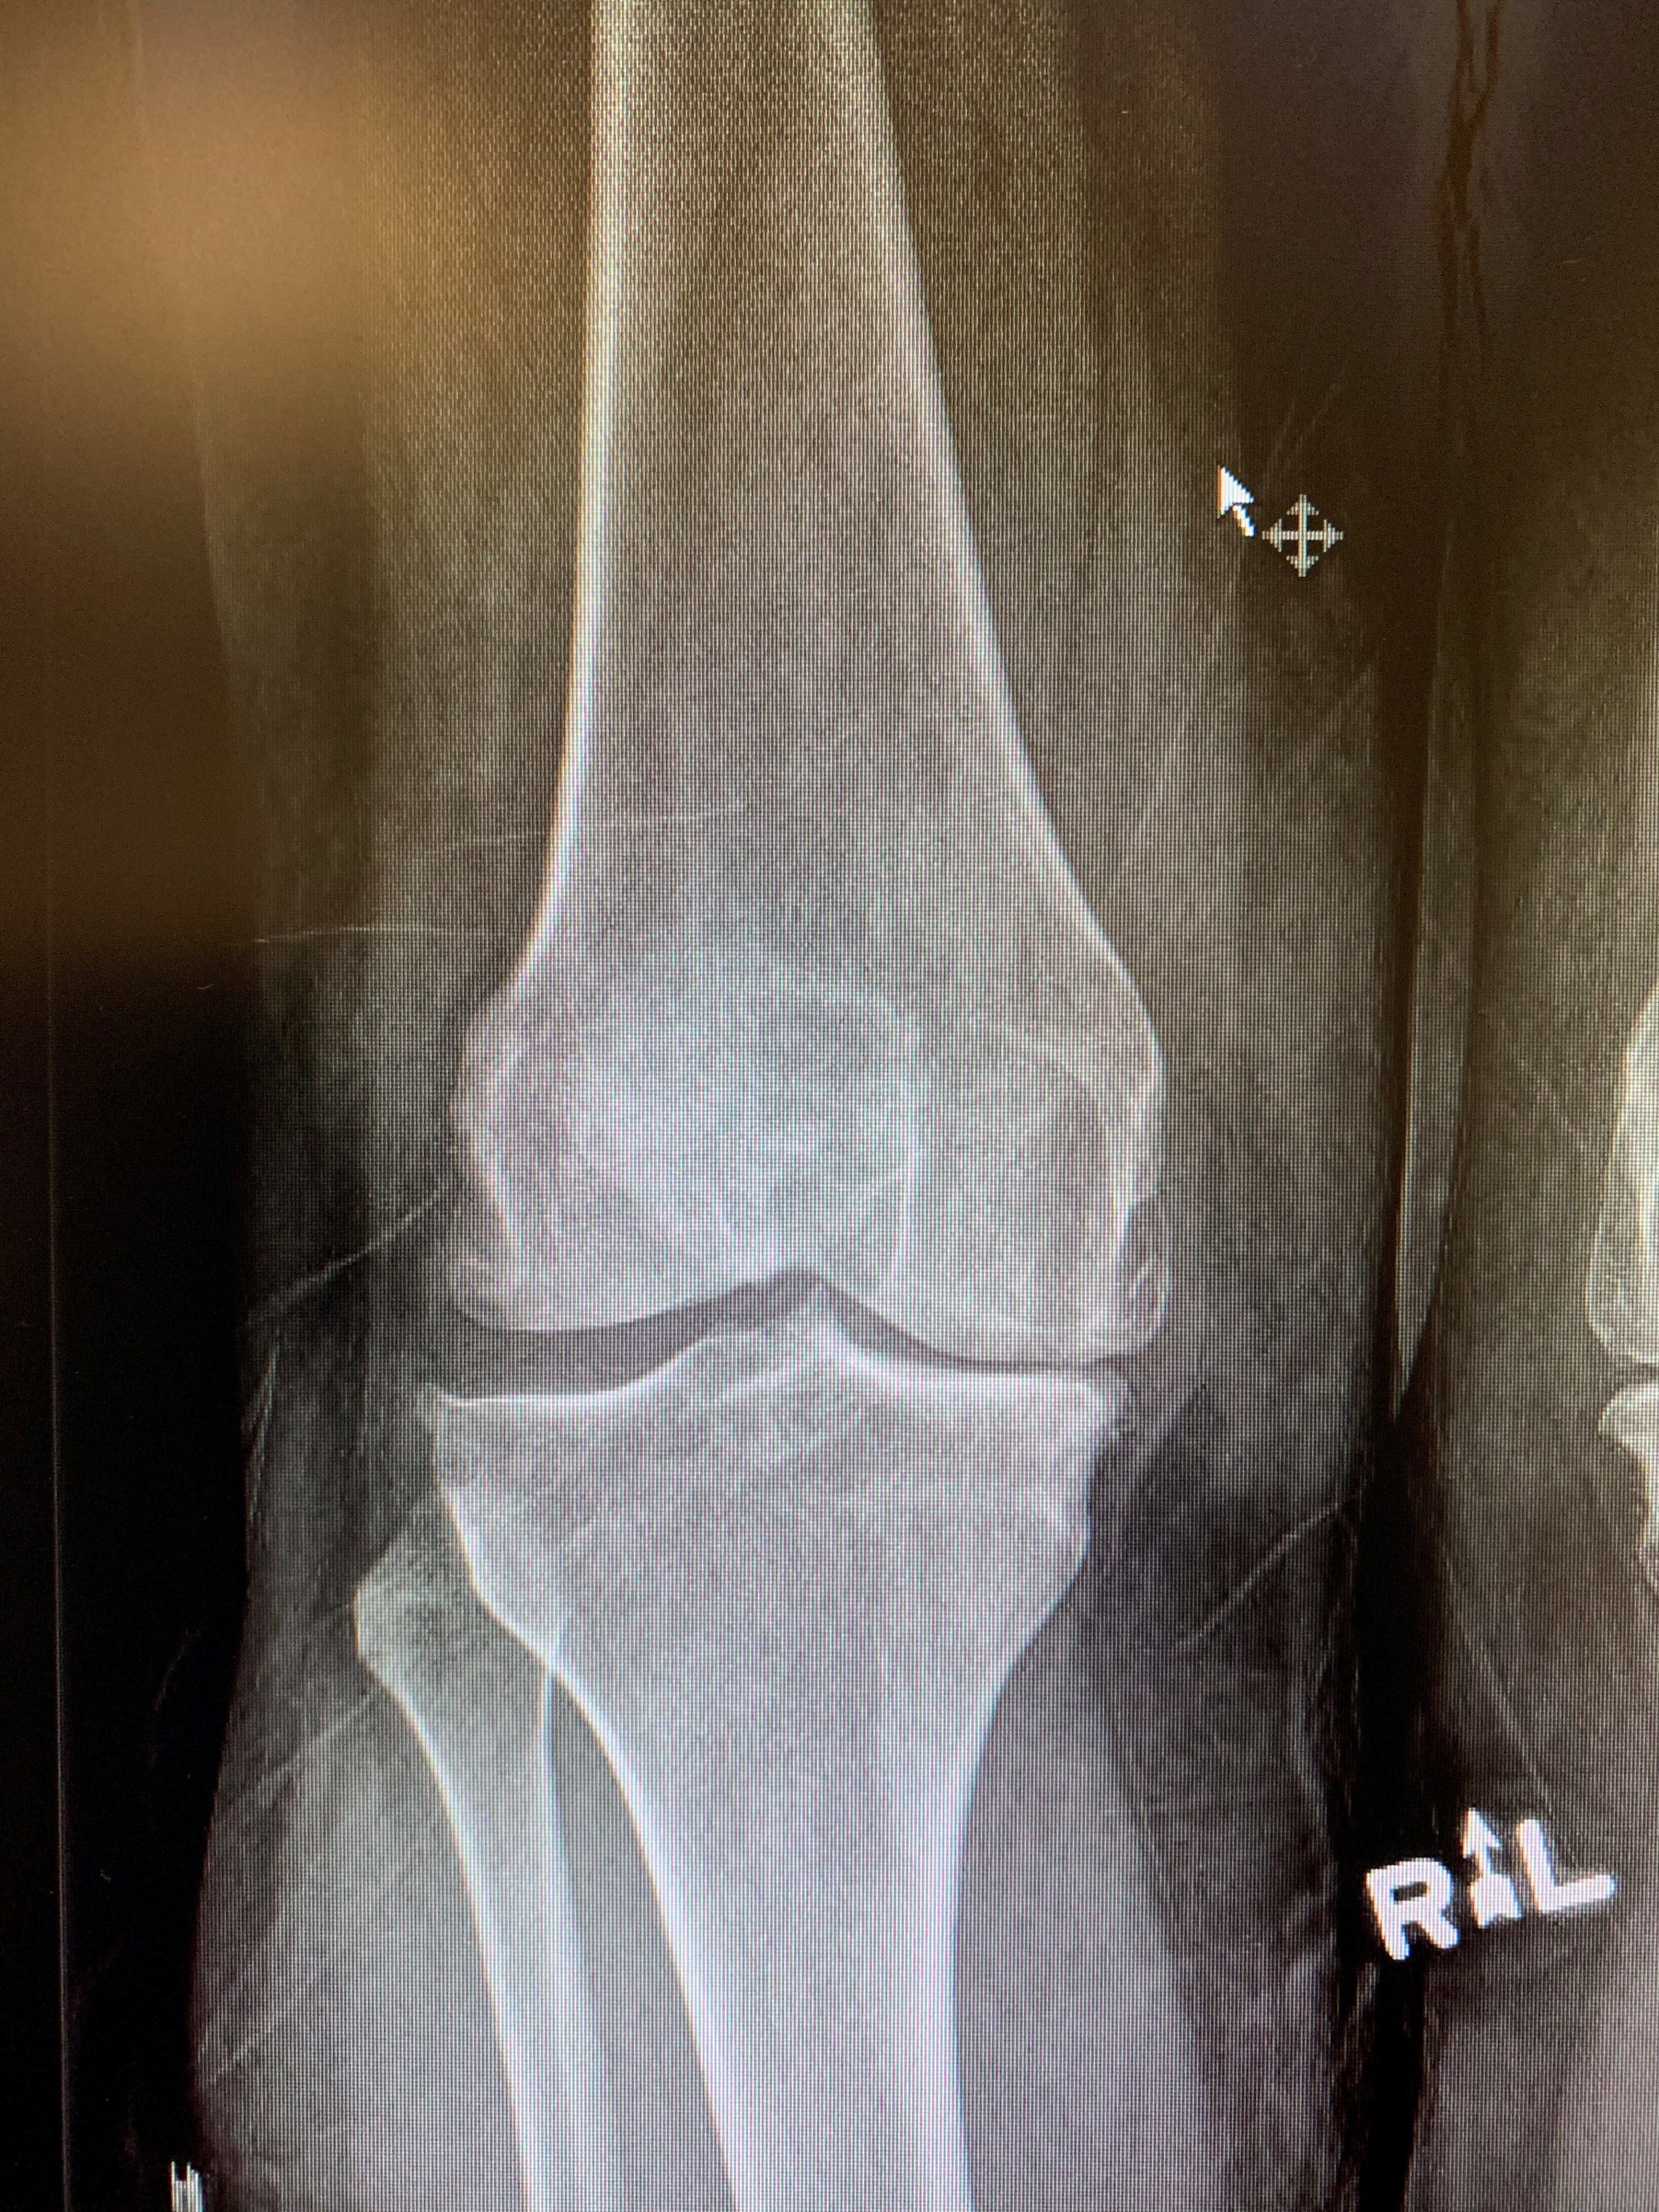

Un hombre de 63 años que fue derivado a nuestra clínica con artritis terminal de rodilla izquierda para su consideración para un reemplazo total de rodilla. Lo evaluamos en nuestra clínica, incluyendo su historial médico y su idoneidad para el manejo quirúrgico de su artritis.

Preoperatorio